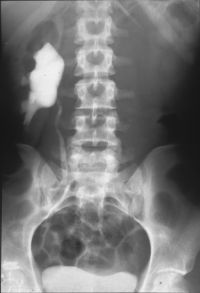

• Abbildung 17: Ureterabgangsstenose mit ausgedehnter Hydronephrose links

5. Ausscheidungsurogramm nach Ureterabgangsplastik, deutlicher Rückgang des weitgestellten NBKS